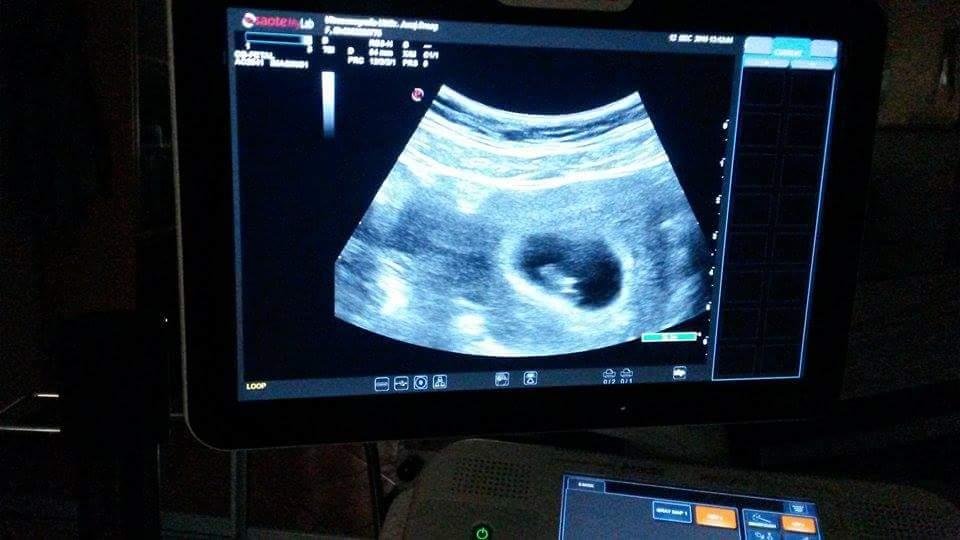

12.12. 2016 mame 6tyzdnov a 6 dni 🙂 a vraj si v brusku od 9.11.2017

tu ta ocinko videl 1x a bol dojaty 🙂 a stastny ako nikdy 🙂 ❤

@csutinko preklep od 9.11.2016